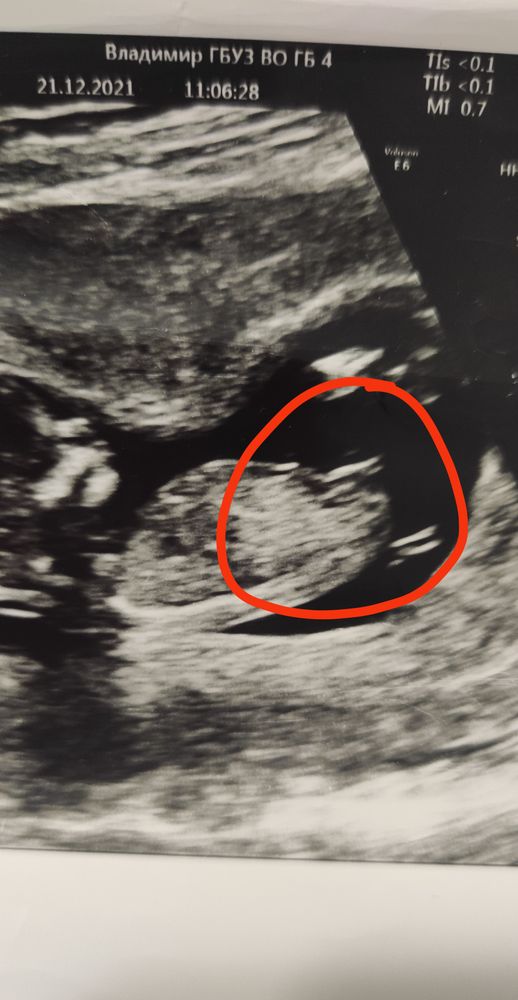

Девчоночка) у меня есть такой же кадр, только в другую сторону в 12 недель)

Snow White

Анастасия, если вот эта полосочка (где должен быть писюн)))) параллельна линии спинки, то это девочка😄